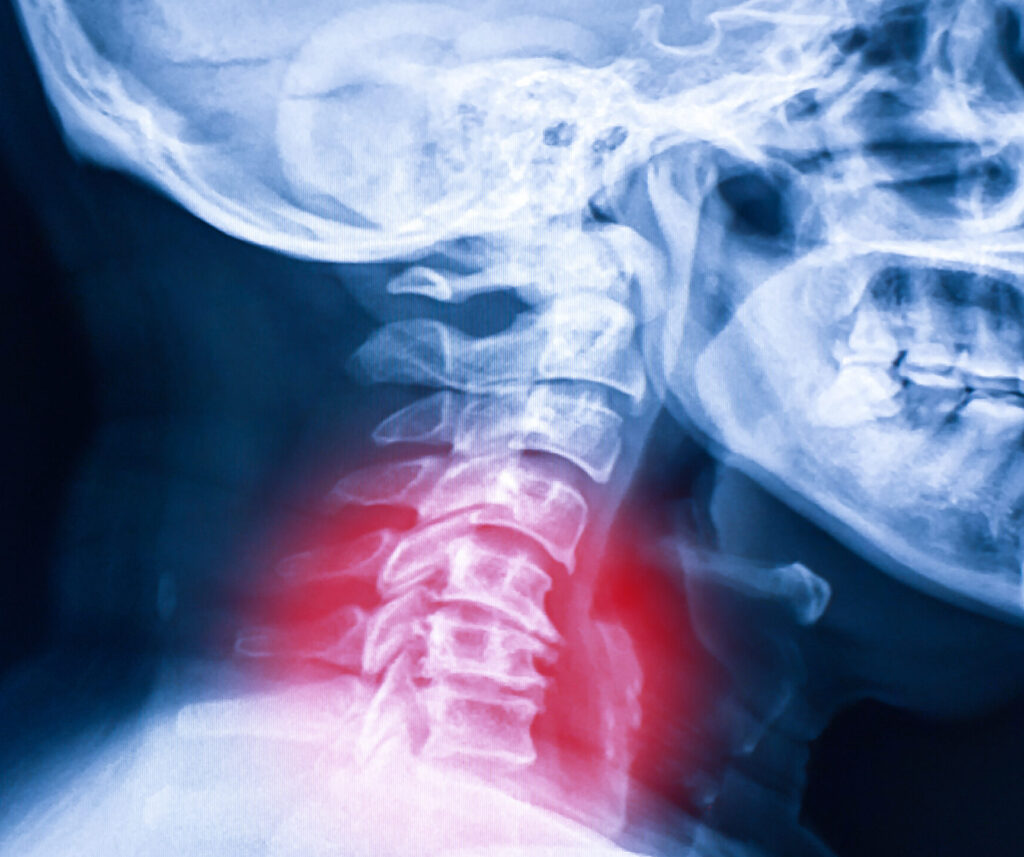

症状は何かしらの原因があります。その原因をまず確認することが改善へのスタートです。骨格の異常はレントゲンで確認することが大切です。

レントゲンで原因を特定、分析にこだわったTLBCテクニック